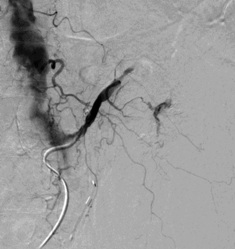

弹簧栓子阻塞胃十二指肠动脉后造影 |

选择性胰背动脉造影未发现明显出血 |